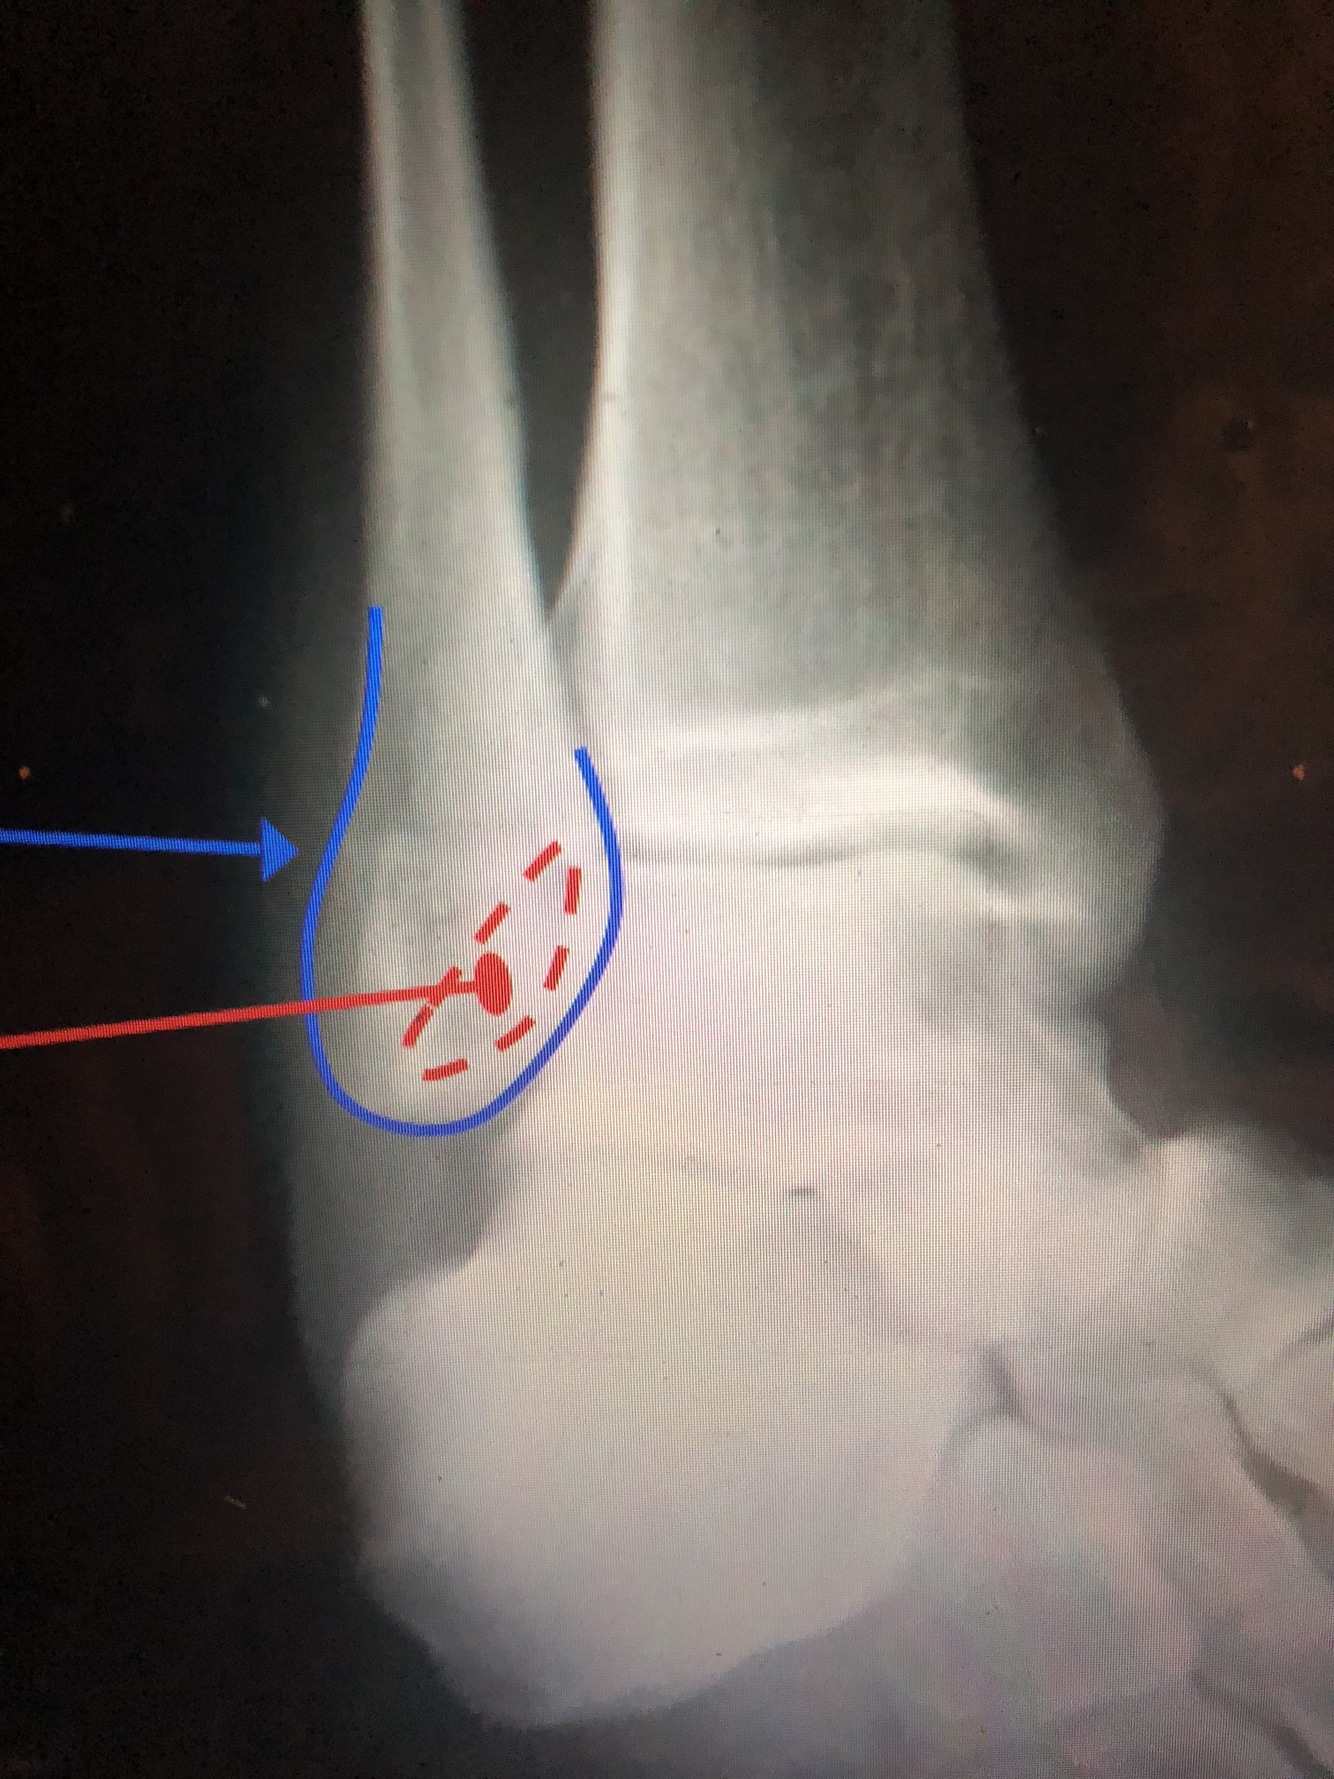

What is the blue line?

Lateral Malleolus

What is the red?

What is the light blue dotted line?

Malleolar Fossa